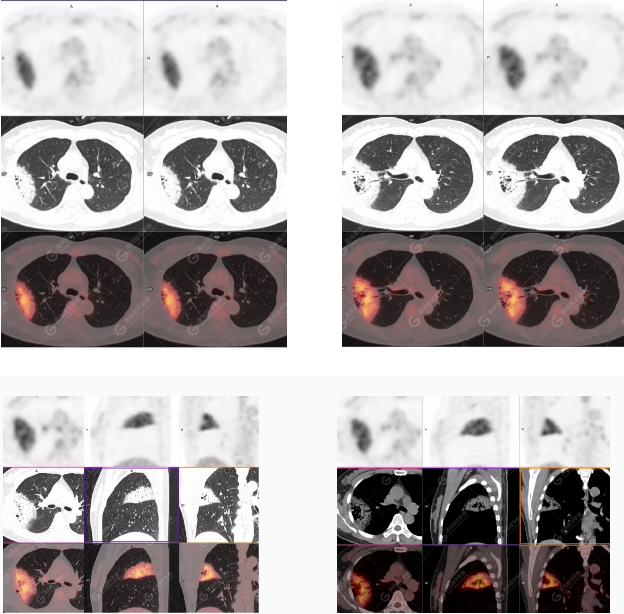

PET/CT影像圖

右肺上葉斑片狀高密度影,部分實(shí)變,邊界清楚,未跨葉間裂;內(nèi)空氣支氣管征、蟲(chóng)蝕樣空洞、周?chē)鷷炚鳎环派湫詳z取增高,SUVmax=4.1。

右肺上葉后段胸膜下片塊狀高代謝病灶,考慮為肺淋巴瘤,請(qǐng)結(jié)合臨床病理。

18F-FDG PET/CT能夠顯示大多類(lèi)型的淋巴瘤,尤其是惡性程度較高的病理類(lèi)型,但對(duì)低度惡性淋巴瘤、尤其是MALT淋巴瘤的顯示能力尚存在爭(zhēng)議。非MALT類(lèi)型PPLSUV明顯高于MALT淋巴瘤,在一定程度上說(shuō)明惡性程度越高,病灶濃聚顯像劑的能力越強(qiáng)。除病理類(lèi)型外,PET顯示淋巴瘤還與腫瘤的部位和大小有關(guān)。肺為含氣臟器,放射性本底低,無(wú)生理性攝取干擾,即使病灶的放射性攝取較低,也能產(chǎn)生足夠?qū)Ρ榷?。肺部MALT淋巴瘤往往因惡性程度較低、病程較長(zhǎng)而發(fā)展成較大病灶,足以攝取較多顯像劑,產(chǎn)生放射性濃聚。此外, PET/CT檢查能夠覆蓋全身,并敏感地顯示全身其它部位有無(wú)病灶,有助于鑒別PPL和繼發(fā)性肺部淋巴瘤。值得注意的是,18F-FDG PET/CT 顯像為非特異性顯像,肺部其他病變(如肺癌、炎癥、結(jié)核等)也可產(chǎn)生放射性濃聚影,僅憑PET圖像往往無(wú)法進(jìn)行準(zhǔn)確鑒別,需密切結(jié)合PET/CT中的CT影像特征及相關(guān)臨床資料,以減少誤診【3】。盡管PPL發(fā)病率低,臨床表現(xiàn)缺乏特異性,但18F-FDG PET/CT表現(xiàn)具有一定特征:1.雙肺多發(fā)、多種形態(tài)病灶,右肺中葉受累常見(jiàn);2.較大腫塊或?qū)嵶儾≡羁缛~分布,內(nèi)有充氣支氣管征;3.大多數(shù)病灶FDG放射性攝取增高。當(dāng)肺部病變具備上述影像表現(xiàn)、而臨床治療效果欠佳時(shí),應(yīng)想到PPL,尤其MALT淋巴瘤的可能性,盡早穿刺活檢,以獲得病理學(xué)診斷【3】。